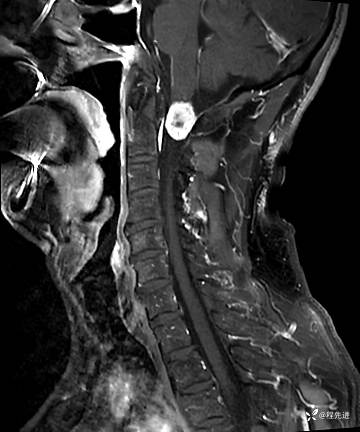

MRI平扫+增强:

T1增强: